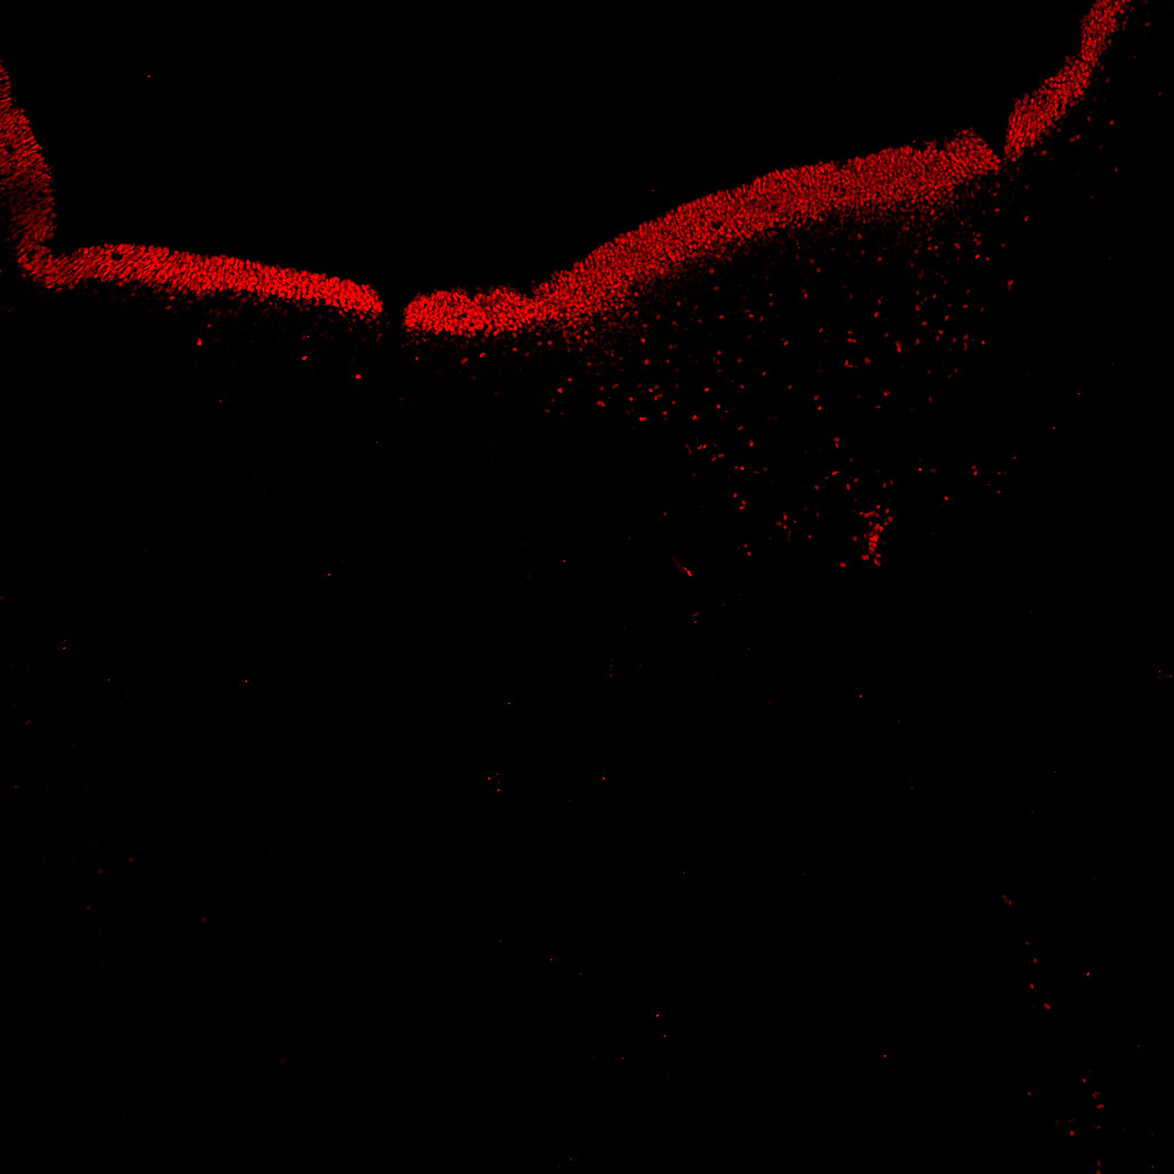

An anatomical analysis of the developing human midbrain from 6 post-conceptional weeks (PCW) to 22 PCW reveals increased tissue complexity, characterized by the emergence of dopaminergic nuclei, as highlighted by immunofluorescence analysis for tyrosine hydroxylase (TH).

DAPI

11PCW human midbrain

TH

Merged